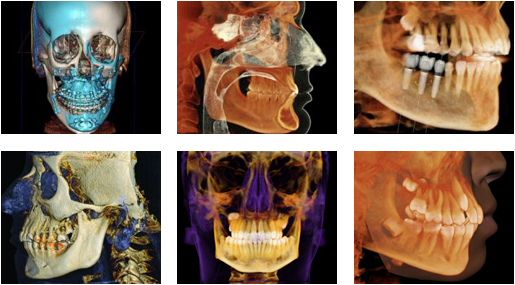

Come and Experience Our latest Technology

Step into a new era of dental care. At our office, we’ve invested in the most advanced technology to bring you safer, faster, and more comfortable treatments than ever before. From digital X-rays and 3D imaging to laser dentistry and same-day crowns, every innovation is designed with your health, time, and smile in mind.

Whether it’s a routine cleaning or a complex procedure, our cutting-edge equipment allows for precise diagnostics and minimally invasive treatments — meaning less discomfort, quicker recovery, and outstanding results. Come see how modern dentistry can make all the difference!